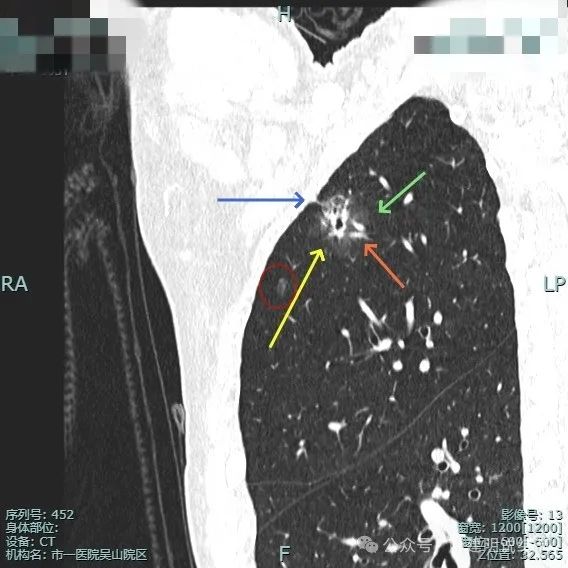

此视角看是典型的浸润性腺癌影像表现:混合密度、毛刺锐利典型、表面分叶、边缘不平、灶内实性成分明显且整体显得杂乱、病灶内部明显扩张的细支气管,磨玻璃成分与正常肺组织之间边界清楚,整体轮廓也清楚。

血管进入以及胸膜牵拉,灶内小空泡征与密度显杂乱,次病灶也有血管进入。

实性成分较明显,扩张的支气管壁显得僵硬,表面分叶明显,边缘细毛刺明显。

毛刺征、混合密度且实性成分杂乱、支气管扩张僵硬、分叶征明显。